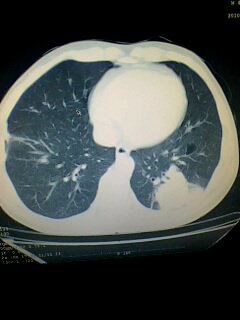

标题: CT28315:咳嗽咳痰咯血半月并胸痛 [打印本页]

标题: CT28315:咳嗽咳痰咯血半月并胸痛

1、纵膈窗效果不好,初步考虑左肺下叶感染性病灶,建议正规抗炎治疗后复查   2、右肺下叶陈旧性病灶伴局部胸膜增厚。

考虑左肺下叶周围型肺癌.图象欠清,请问病人贵更?

考虑左肺下叶周围型肺癌.

图像资料欠清,建议强化,考虑周围型肺癌。

左下肺肿块影,深分叶,考虑肺癌。

左下肺球形病灶,考虑:1:球形肺炎;2:周围型肺癌不除外,建议治疗后复查

不排除左肺下叶周围型肺癌可能!建议穿刺活检!

考虑左肺下叶周围型肺癌。

考虑左肺下叶周围型肺癌并阻塞性肺炎。

考虑左肺下叶周围型肺癌